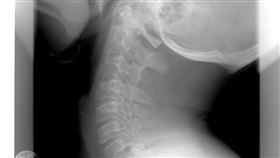

6旬翁「頭頸分離」命危!醫1招奇蹟保命

奇蹟!日前在中國廣州有一名阿伯因為發生意外,導致頭頸...